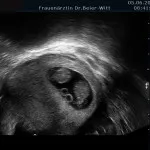

Frühschwangerschaft:

Ultraschall_10